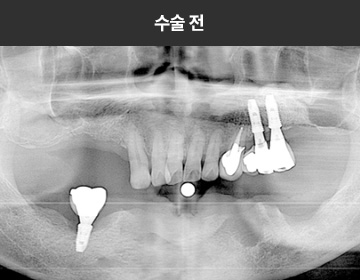

BMP를 이용한 수술 사례      I

치료 기간 : 2023.03.22 ~ 2023.09.15

* 상기 사례의 경우, 해당 의료기관에서 진료를 한 환자분의 동의를 얻어 사용되었습니다. * 치료 전후의 사진은 동일 인물과 동일한 조건에서 촬영 되었음을 알려드립니다.

* 모든 수술 및 시술은 개인에 따라 부작용고지 : 임플란트치료는 치료 후 감염,

염증, 연조직합병증, 출혈, 감각이상 등의 부작용이 있을 수 있습니다.

의료진과 충분히 상의 후 신중하게 결정하시기를 바라겠습니다.